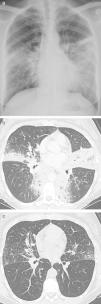

Case PresentationsCase 1A 44-year old female non-smoker presented with cough and dyspnea. She was afebrile, and physical examination was unremarkable. Her lab tests showed elevated CRP (122mg/L). Pulmonary function tests showed normal spirometry (FEV1 94%, FVC 96% predicted), normal lung volumes (TLC 102%, FRC 119% predicted) and reduced DLCO (68% predicted). Chest imaging showed bilateral air space disease and peribronchovascular nodules (Fig. 1a,b). Core needle biopsy showed thickened lung interstitium, dense lymphoplasmocytic infiltrate, fibrotic blood vessels and 30–40 IgG4+ plasma cells per high power field (hpf). Serum IgG4 was 573mg/dl (normal range: 3–201mg/dl). On follow-up (18 months from diagnosis), pulmonary symptoms resolved spontaneously and radiological findings had partially regressed (Fig. 1c). Spirometry, lung volumes and DLCO did not change. Several months after discharge, a diagnosis of dacryoadenitis was made following a complaint of dry eyes.